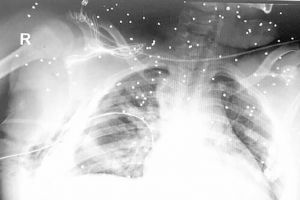

الطفل إبراهيم بمجمع السلمانية الطبي